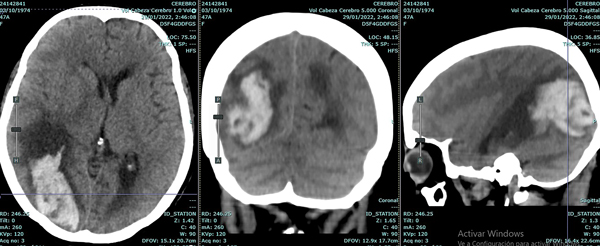

Se trata de una mujer de 47 años, portadora de angeítis de Wegener con compromiso pulmonar severo y otras comorbilidades, que requirió asistencia ventilatoria mecánica (AVM) por insuficiencia ventilatoria y posteriormente traqueostomía. Luego de varios días en AVM desarrolló en el transcurso de pocas horas estupor y deterioro de la respuesta motriz; la TC de encéfalo sin contraste mostró hidrocefalia aguda obstructiva por lesión de fosa posterior (Figura 6).

Figura 6: Tomografía computada del encéfalo donde se aprecia edema cerebeloso con compresión del tronco cerebral e hidrocefalia supratentorial aguda.